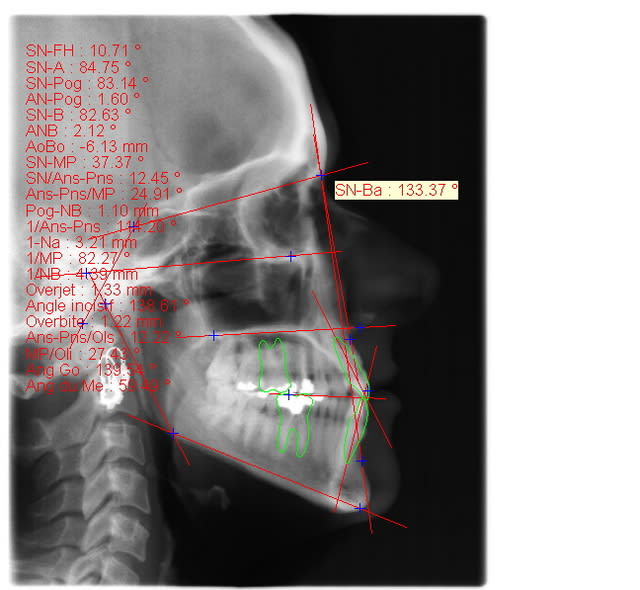

voici de la cas d'un jeune dame de 23 ans qui présente une full classe III subdivision Droite (associée à des compensations incisives de classe III), sur un terrain hyperdivergent. on note un encombrement inferieur d'environ 2 mm et une abrasion des bords triturants des incisives inf (Motif de la consultation)

on notera egalement de face une déviation de la pointe du menton vers la gauche.